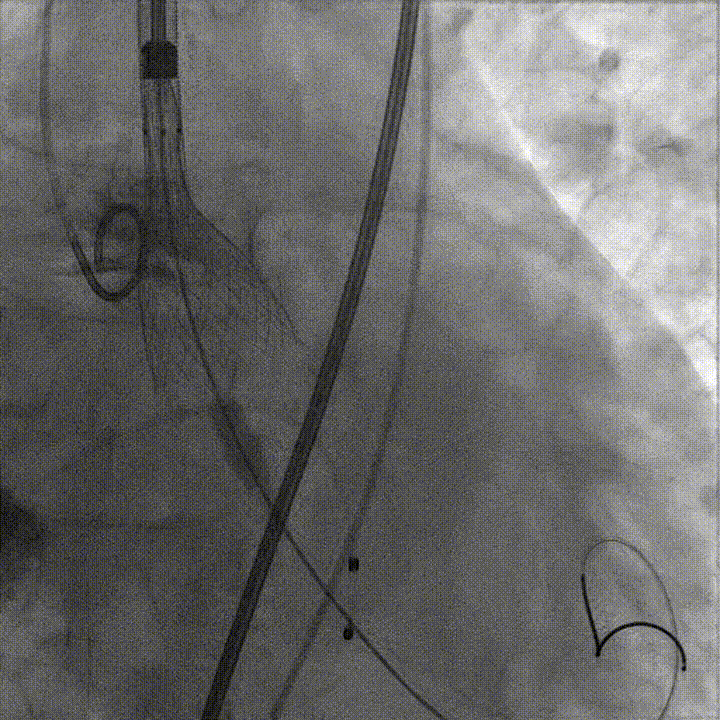

首次释放瓣膜尝试零位释放,当瓣膜释放到一半时行主动脉根部造影,发现瓣膜释放位置偏低,遂回收瓣膜重新定位后再次释放,当瓣膜释放一半时再行主动脉根部造影,发现瓣膜位置良好,遂完全释放瓣膜。

完全释放瓣膜后,经胸超声心动图显示存在轻微反流;术后造影复查显示瓣膜释放良好,轻微反流,患者情况明显改善。最后撤出导管导丝,边撤边造影,确认没有入路相关并发症,圆满完成手术。